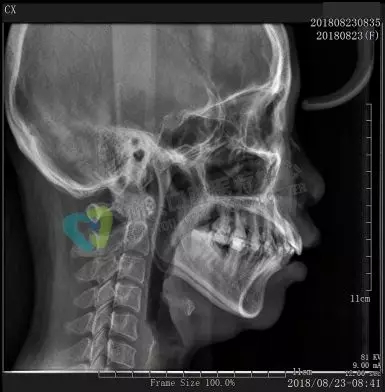

口腔全景牙片,是通過一次拍攝將全口牙齒和頜骨的影像清晰的顯示在一張X光片上,可以清晰、完整的顯示上頜骨、下頜骨全貌,上下頜牙列情況,牙槽骨情況,能夠清晰顯示上頜竇腔、竇壁、竇底情況以及顳頜關(guān)節(jié)情況,并對(duì)頜骨周圍疾病的診斷提供準(zhǔn)確有效的幫助。